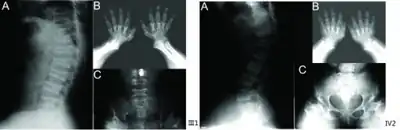

a) Anterior beaking of vertebral bodies b) short metacarpals and phalanges, cone-shaped epiphyses c) scoliosis, small femoral heads, flared metaphyseal borders -

Skeletal radiography

Accurate assessment of plain radiographic findings remains an important contributor to diagnosis of pseudoachondroplasia. It is noteworthy that vertebral radiographic abnormalities tend to resolve over time. Epiphyseal abnormalities tend to run a progressive course. Patients usually suffer early-onset arthritis of hips and knees. Many unique skeletal radiographic abnormalities of patients with pseudoachondroplasia have been reported in the literature.[2][7][4]

- Oval shaped vertebrae with anterior beak originating and platyspondyly demonstrated on lateral radiographs of the spine.

- Normal widening of the interpedicular distances caudally demonstrated on anteroposterior radiographs of the dorsolumbar region. This is an important differentiating feature between pseudoachondroplasia and achondroplasia.

- Odontoid hypoplasia may occur resulting in cervical instability.